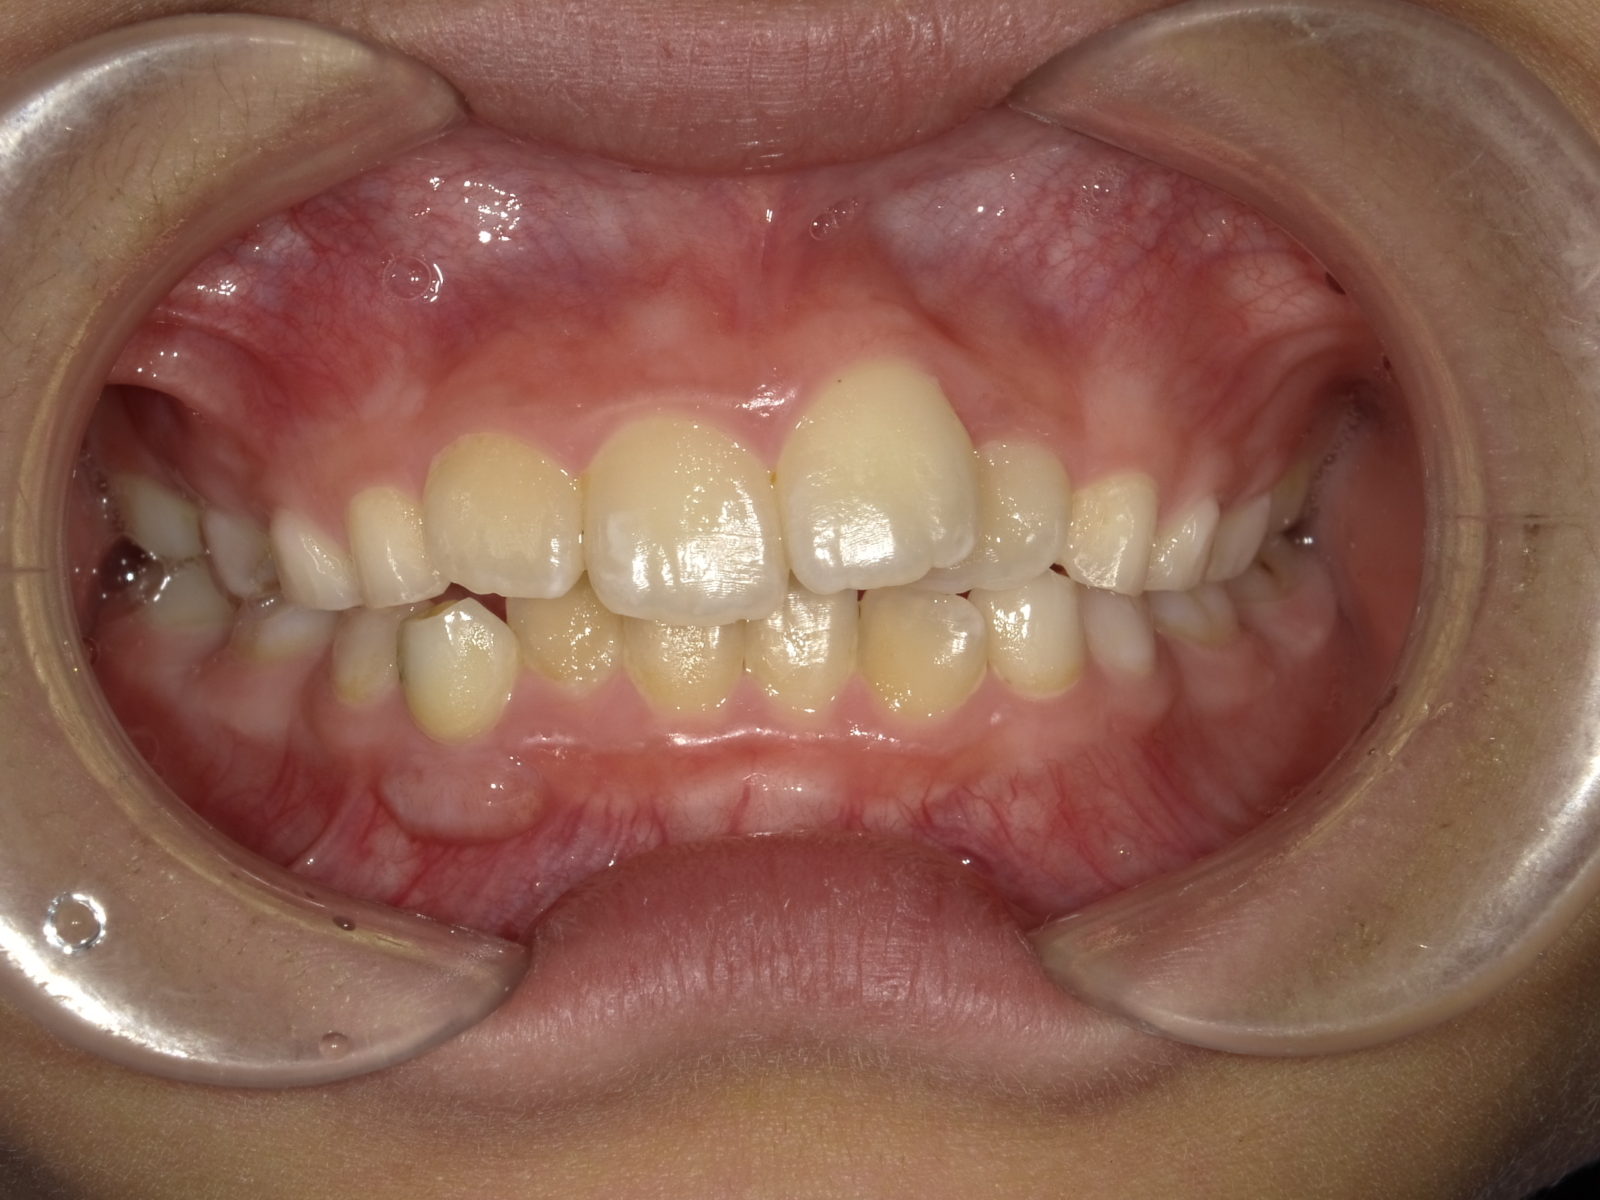

顎顔面矯正の説明をする前に、「なぜ子供の歯並びが悪くなるの?」に関してお答えします。

簡単にお伝えすると、歯が生える土台の「顎」が昔と比べて小さくなっているためです。

「3人掛けのベンチに5人が座る」ことをイメージしてみてください。

きれいに座れず飛びたす人もいますよね?

歯も同じです。

狭い顎に無理矢理歯が並ぼうとするので、ガチャガチャになるのです。

一般的に行われている矯正は、この状態を力技で並べます。

しかし、それでは根本的な改善にはなりません。その理由として、一度並べた歯が時間の経過とともに後戻りしてしまうことからもわかると思います。

つまり、歯が適切に並ぶように「顎のスペースを広げる」ことが重要になります。